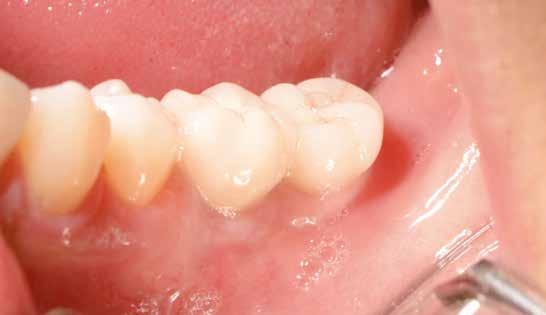

1. ábra: A műtét előtti szituáció, megfigyelhető az implantátumok közötti konkáv terület, ahova könnyen beragad az ételmaradék, és könnyen kialakul a periimplantitis.

Egy 47 éves páciens jelentkezett nálunk egy alsó, hátsó foghiánnyal, ahol jelentős csontfelszívódást tapasztaltunk a moláris fogak korábbi eltávolítása miatt (1. ábra). Két implantátum körül is volt ínyrecesszió, illetve a keratinizált íny mennyisége minimális volt (kevesebb, mint 1 mm). 4 hónappal az implantációt követően ínykorrekciót végeztünk.

16. ábra: Klinikai kép az implantátumok körüli lágyszövetről a végleges pótlásátadás után. – 17. ábra: Klinikai kép az implantátumok körüli lágyszövetről egy évvel az átadást követően. – 18. ábra: Klinikai kép az implantátumok körüli lágyszövetről két évvel az átadást követően. – 19. ábra: Klinikai kép az implantátumok körüli lágyszövetről öt évvel az átadást követően.